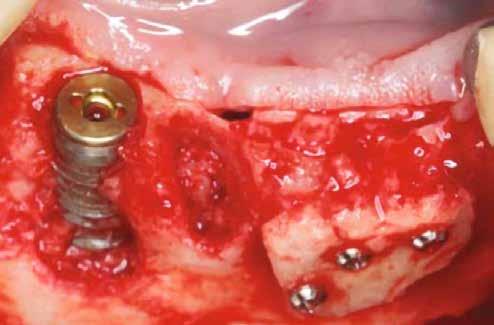

A feltárást csontpótlás kísérheti, az új implantátum behelyezéséhez szükséges alveoláris gerinc előkészítése érdekében (9).

A regeneratív periimplantitis kezelése

A páciens szájüregi egészségi állapotának a felmérése (1 táblázat).

Kockázati tényezők: túl sok cementet tartalmazó kötőanyag szubmukozálisan.

Implantátum hely: 2.1; Straumann, lágyrész-szint, átmérő: 4,1 mm, hossz: 10 mm, Standard Plus, nyaki rész 1,8 mm. Gyógyszeres kezelés: Amoxicillin 500 mg és Metronidazol 400 mg naponta háromszor 7 napig.

A műtét után klórhexidin szájöblítés (0,2%) történt naponta kétszer 1 percig, 4 héten keresztül, majd 6 hónapos fenntartó gondozás.

Célok

1. Az implantátum funkciójának fenntartása.

2. A periimplantáris gyulladás megszüntetése.

3. Az implantátum körüli intraosszeális defektus regenerálása.

4. A periimplantáris gyulladás kiújulásának megelőzése érdekében sebészi hozzáférést terveztek a röntgenfelvételen jól látható, felesleges rögzítőcement eltávolítására.

Összefoglalás

A regeneratív kezelést követő 3 hónap után a gyulladás megszűnt. A kezelés előtt a középső periimplantáris nyálkahártyán észlelt, sinus felőli szivárgás megszűnt. A klinikai vizsgálat 12 hónap múlva a periimplantáris szondázási mélység csökkenését mutatta, a periimplantáris gyulladás megszűnésével együtt.

Anyagválasztás:

Geistlich Bio-Oss csontpótló granulátum (méret: 0.25–1 mm), Geistlich Bio-Gide membrán (méret: 13 mm x 25 mm).